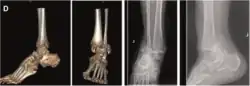

| Pronation-External rotation |

|

![]() |